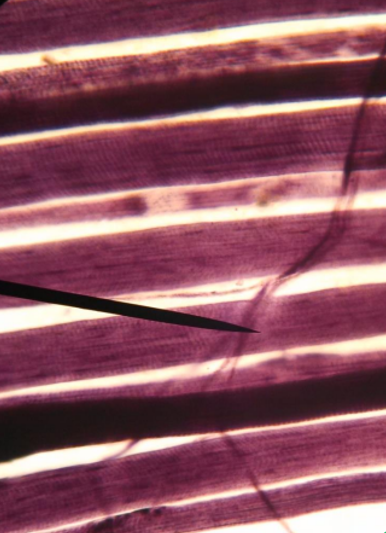

What muscle is this?

Cardiac muscle

What is the pointer on?

intercalated disc

What are the black arrows pointing to?

intercalated discs